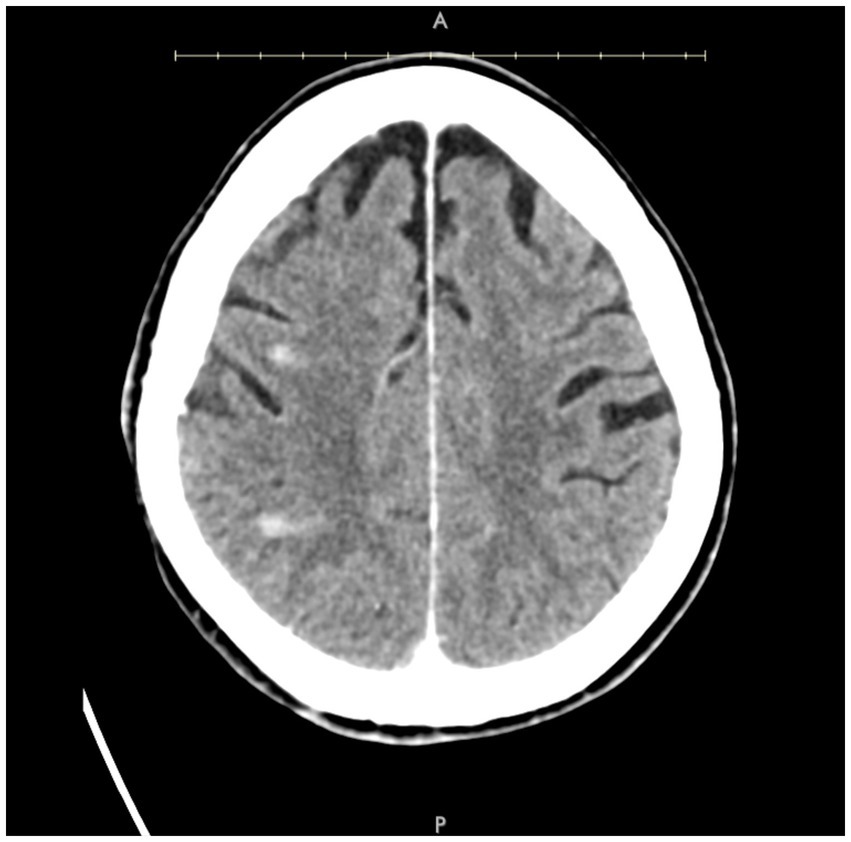

Figure 3. Axial post-contrast CT demonstrating small areas of enhancement within the right MCA territory.

A patient in their 70s presented with left-sided hemiplegia, left facial droop, and dysarthria. CTA demonstrated greater than 95% stenosis in the right ICA. Computed tomography imaging showed scattered right middle cerebral artery (MCA) infarcts (Figure 3). The patient was at high risk for surgery secondary to numerous medical comorbidities, including hypertension, peripheral vascular disease s/p peripheral bypass with subsequent thrombosis, left above-the-knee amputation, and bilateral renal stenosis. Thus, they underwent IVL and CAS with 2 episodes of sonic pulses (Figure 4). Right-sided radial access was attempted but unsuccessful in this patient; ultimately, femoral arterial access was established. Post-procedurally, the patient developed a right radial pseudoaneurysm and a hematoma at the right femoral access site, which was associated with acute blood loss anemia (hemoglobin at 6.6 g/dL) that normalized after transfusion. No surgical intervention for the femoral access site was required. Post-angiogram ultrasound findings showed PSV of 110 cm/s in the right CCA and 122 cm/s in the right ICA with a peak systolic ICA/CCA velocity ratio of 1.1 and no stenosis in the right ICA. The patient’s hospital stay was 9 days, followed by 2 weeks of inpatient acute rehabilitation. The patient did not establish neurosurgical follow-up; however, at the time of discharge from acute rehabilitation, the patient had mild weakness in the left upper extremity with improved finger dexterity and coordination.